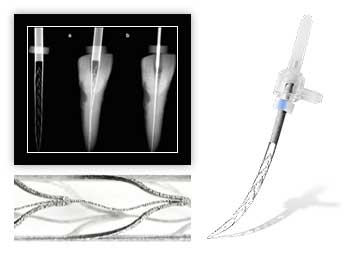

Медицинский центр «Интердентос» основан в 1998 году. Наши стандарты технического оснащения и контроля качества, подбора и подготовки врачей, защиты пациентов от инфекций являются чрезвычайно высокими, что подтверждено независимыми экспертами в области стоматологии. У нас работают дипломированные специалисты, оказывающие весь спектр стоматологических услуг. Опытные терапевты и пародонтологи, хирурги и ортопеды справятся с любой задачей благодаря своей высокой квалификации и индивидуальному подходу к каждому пациенту. Мы не просто лечим зубы, мы комплексно подходим к решению заболеваний полости рта. Такой уникальный подход к лечению позволяет нам гарантировать не только качественное оказание помощи, но и предсказуемо высокий результат. Спектр услуг клиники обширен: имплантация зубов, протезирование, терапевтическое лечение зубов любой сложности, исправление неправильного прикуса, лечение пародонтита. А также услуги эстетической стоматологии – отбеливание, художественные реставрации из керамики, фарфора, установка виниров и люминиров. Мы смело можем заявить - наши врачи могут ВСЕ в стоматологии!